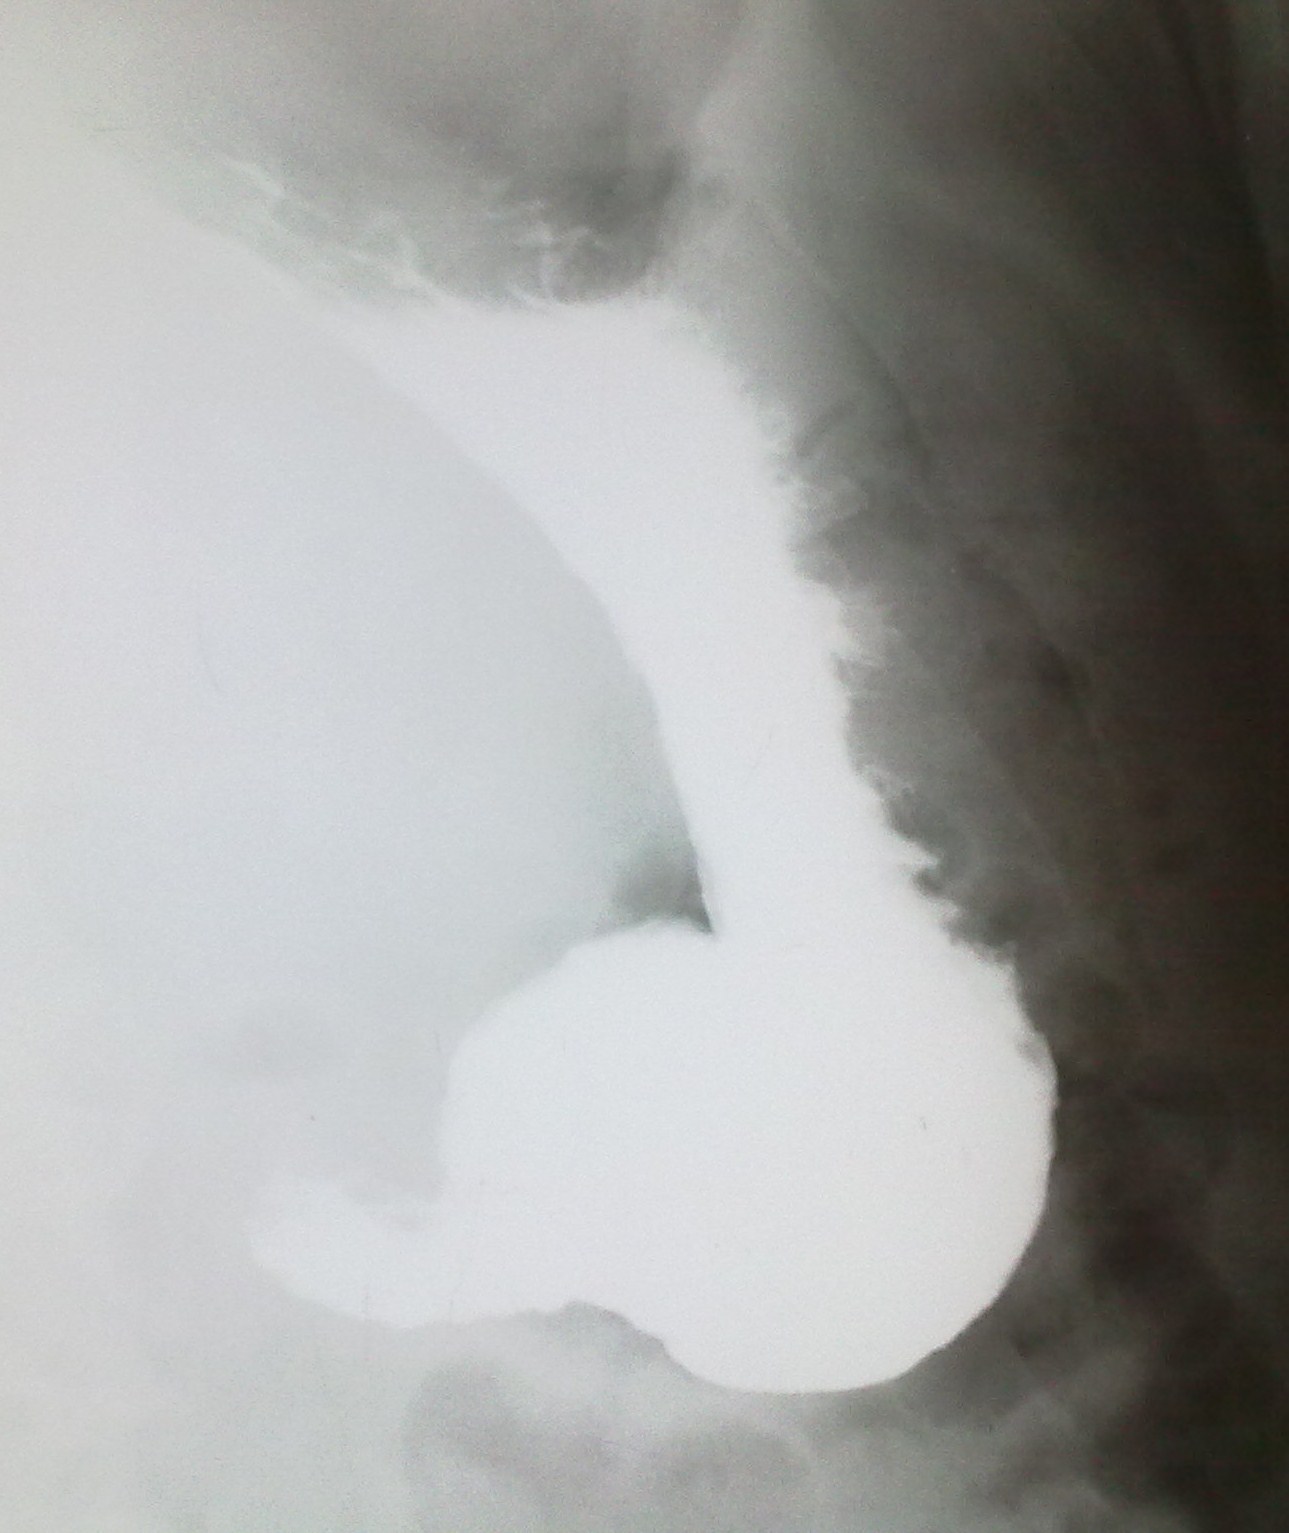

С искренней симпатией и желанием помочь представляю варианты не "а-ля", а такие какие должны быть.

Поэтому, если позволите, то по методике. Представлено 5 снимков. Каких нет? Нет прямого в вертикальном положении с контрастированной 12-перстной кишкой; нет лежа на животе с приподнятым левым боком и контрастированным пищеводом (именно в этой проекции определяется ГПОД), нет лежа на спине с приподнятым правым боком (для оценки пилоробульбарной зоны), нет левого бокового снимка стоя после снимков лежа (для оценки купола и задней стенки желудка).

И еще - гиперпластический гастрит, все-таки, достаточно редок, хронический гастрит, в основном, атрофический; неровность контура по большой кривизне в антральном отделе - является признаком хр гастрита (выход складок на контур); двуслойное содержимое луковицы 12-перстной кишки (газ и барий) - р-признаки бульбостаза (бывет еще 3-хслойное содержимое - барий-жидкость-газ) - косвенного признака патологии желчевыводящих путей.